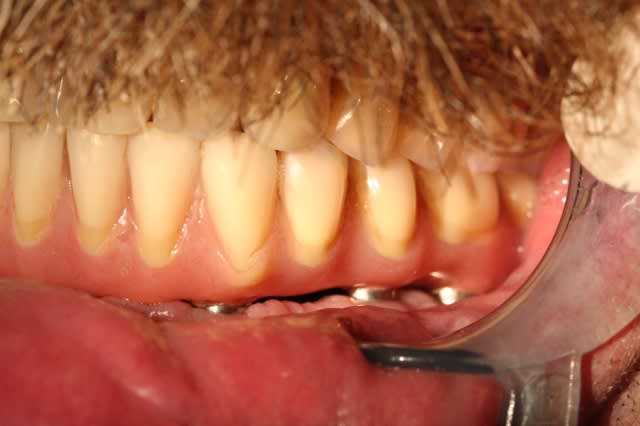

> j'avais promis de montrer la suite et la fin du cas.

>

> Alors voilà: empreinte pick-up mixte (silicone et plâtre snowhite), RIM avec

> cire calée sur des piliers hauts, et aujourd'hui retrait des implants

> provisoire et vissage de la prothèse.

il s'agit de dents et fausse gencive en résine.

l'extension se calcule, c'est 1.5 X la distance entre 2 droites parallèles (une qui passe par les bords postérieurs des implants les plus distaux et l'autre qui passe par le milieu de l'implant le plus antérieur)

ici je suis à X 1.6 , j'ai aussi,en quelque sorte, une "extension antérieure" du fait que les incisives sont vestibulées par rapport à l'implant médian et la patiente n'a pas non plus des masseters surpuissants.

cette solution est éprouvée et sur le prochain, je tacherai juste de donner une petite inclinaison distale aux implants distaux (comme l'avait suggéré noahaxeltiger)..1 mm de gagné c'est toujours interessant.